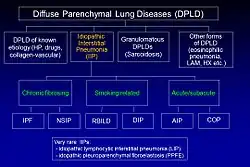

La FPI pertenece a un gran grupo de más de 200 enfermedades pulmonares llamadas neumopatías intersticiales (NI) que se caracterizan por afectar al intersticio pulmonar,[2] el tejido entre los alveolos pulmonares.La FPI es una enfermedad diferenciada entre las neumonías intersticiales idiopáticas (NII), las cuales a su vez son un tipo de NI, también conocidas como neumopatías parenquimatosas difusas (NPD).

La clasificación de 2002 de la American Thoracic Society/European Respiratory Society (ATS/ERS) para las NII se actualizó en 2013.[2] En esta nueva clasificación existen tres categorías principales de NII: NII principal, NII raras y NII inclasificables. Las NII principales se agrupan en NI fibrosantes crónicas, que incluye la FPI y la neumonía intersticial no específica [NINE]), las NI relacionadas con el tabaquismo (por ejemplo, la neumopatía intersticial-bronquiolitis [NI-B] y la neumonía intersticial descamativa [NID]; y las NI agudas/subagudas (por ejemplo, neumonía organizante criptogénica [NOC] y neumonía intersticial aguda [NIA].[2]

La siguiente imagen muestra la nueva clasificación de las NII